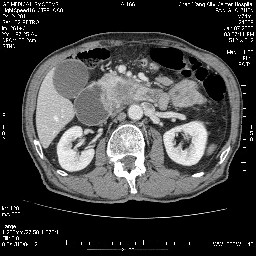

女,74岁,呕吐10余日

十二指肠降段扩张,水平段狭窄成鼠尾状,肠壁明显增厚,胰腺勾突增大成不均匀强化,其内可见低密度区,胆囊增大,1十二指肠水平段腺癌侵犯胰腺勾突可能大,2胰腺癌侵犯十二指肠(只有胆囊增大没有肝内外胆管扩张不好解释)代除外.

十二指肠降段扩张,水平段狭窄成鼠尾状,肠壁明显增厚,胰腺勾突增大成不均匀强化,其内可见低密度区,胆囊增大,1十二指肠水平段腺癌侵犯胰腺勾突可能大,2胰腺癌侵犯十二指肠 。

今日手术结果:胰腺钩突癌侵犯十二直肠,腹腔淋巴结转移.